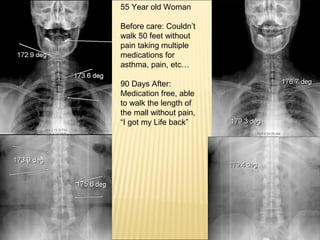

55 Year oldWoman Before care: Couldn’t walk 50 feet without pain taking multiple medications for asthma, pain, etc… 90 Days After: Medication free, able to walk the length of the mall without pain, “I got my Life back”

14% reduction inScoliosis in 90 days in a Patient 68 Y.O. High BP, High Cholesterol, High Blood Sugar Before After